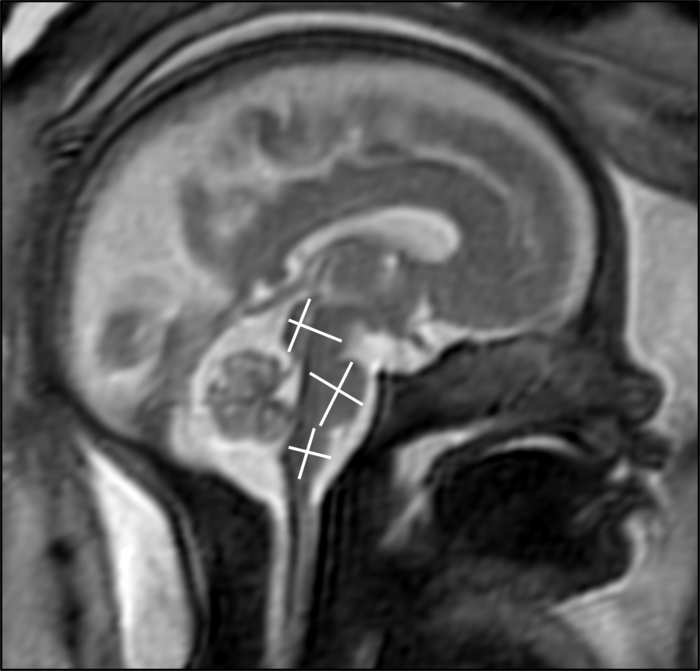

Dr. Stöcklein and colleagues used fetal MRI to study 33 patients with COVID-19 infection during pregnancy. The patients were roughly 28 weeks into their pregnancies, on average, with symptom onset occurring at a mean of just over 18 weeks into the pregnancy. The most common maternal symptoms were loss or a reduced sense of smell and taste, dry cough, fever and shortness of breath.

Two board-certified radiologists with several years of experience in fetal MRI evaluated the scans. They found that the brain development in the assessed areas was age-appropriate in all fetuses. There were no findings indicative of infection of the fetal brain.

“In our study, there was no evidence that a maternal SARS-CoV-2 infection has any effect on the brain development of the unborn child,” Dr. Stöcklein said. “This fact should help to reassure affected parents.”